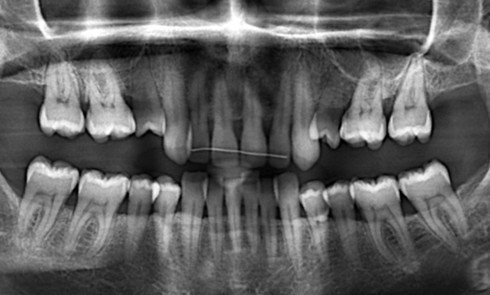

Article réservé à nos abonnés Traitement d’une Classe II subdivision gauche avec DDM dans un contexte de mésodivergence

Présentation du cas Kenny, âgé de 12 ans, sans antécédent orthodontique, consulte pour ses malpositions dentaires. Examen exobuccal (fig. 1a-c)...